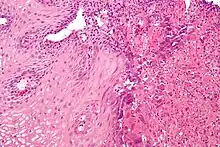

Microscopic Slide of Infectious Esophagitis

Infectious esophagitis

Esophagitis happens due to a viral, fungal, parasitic or bacterial infection. More likely to happen to people who have an immunodeficiency. Types include: